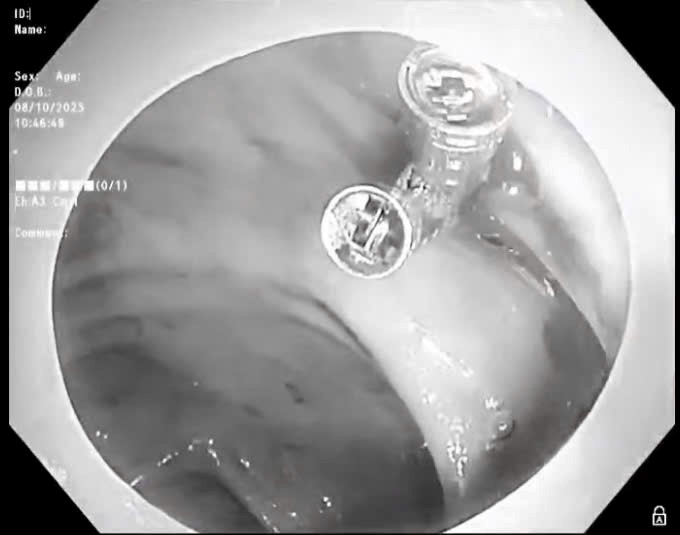

Friday 2025-10-17 05:02Vừa qua, Bệnh viện đa khoa (BVĐK) Sóc Sơn đã tiếp nhận bệnh nhân Đỗ Văn P (69 tuổi) ở Sóc Sơn, được người nhà đưa đến bệnh viện cấp cứu. Các bác sĩ xử trí kịp thời ca bệnh sốc...